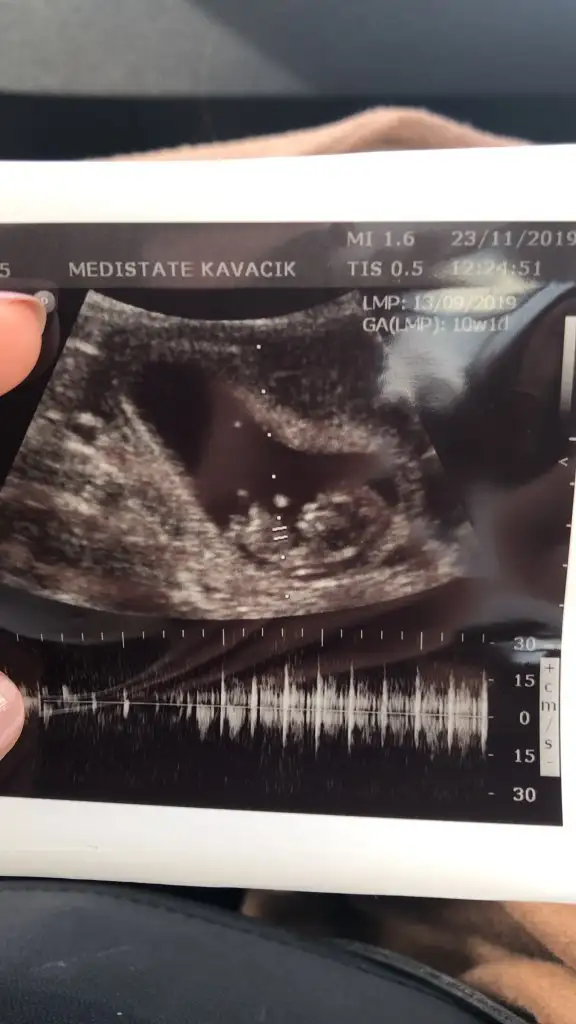

Kızlar cikinti dediginiz hangisi

benimki ne oluyo ozaman erkekmi kızmı kafam karisti ya ordaki sey bacak degilmi 🤔

Tekrar bakar mısınız